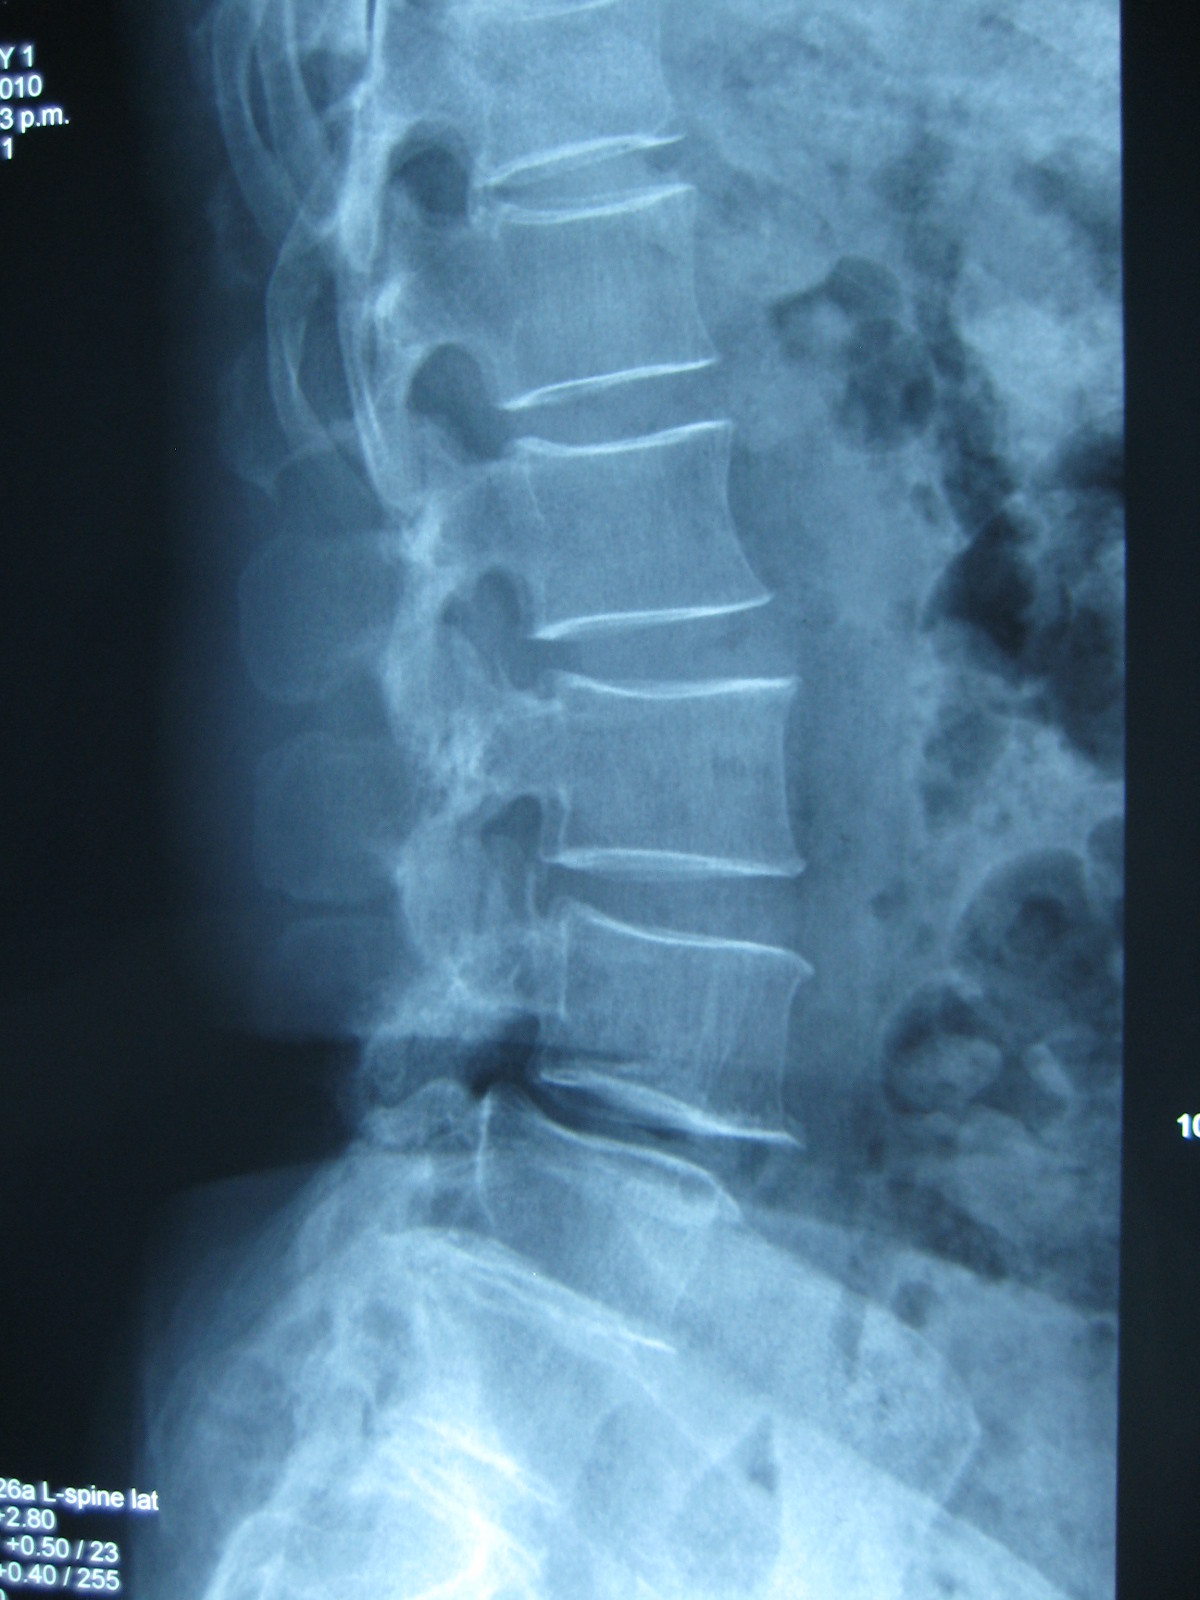

腰椎滑脱2度

病例讨论:腰4椎体双侧峡部裂并2度滑脱 [病例帖]